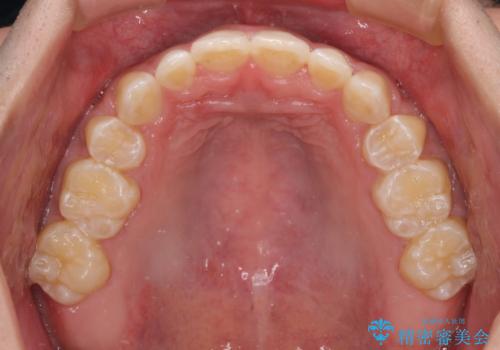

口元の突出感を改善 受け口傾向の咬み合わせの抜歯矯正

- 受け口傾向の咬み合わせと口元の突出感を気にして来院された患者様です。

受け口傾向特有の狭い上顎歯列であったため、歯列の拡大を補助装置で行い、下顎歯列全体を後方に移動させることとしました。

奥歯の咬み合わせを改善させた後、上下左右の小臼歯(下顎は残存乳歯)を計4本抜歯し、ワイヤー装置にて口元の突出感を改善しながら咬み合わせを整えることとしました。